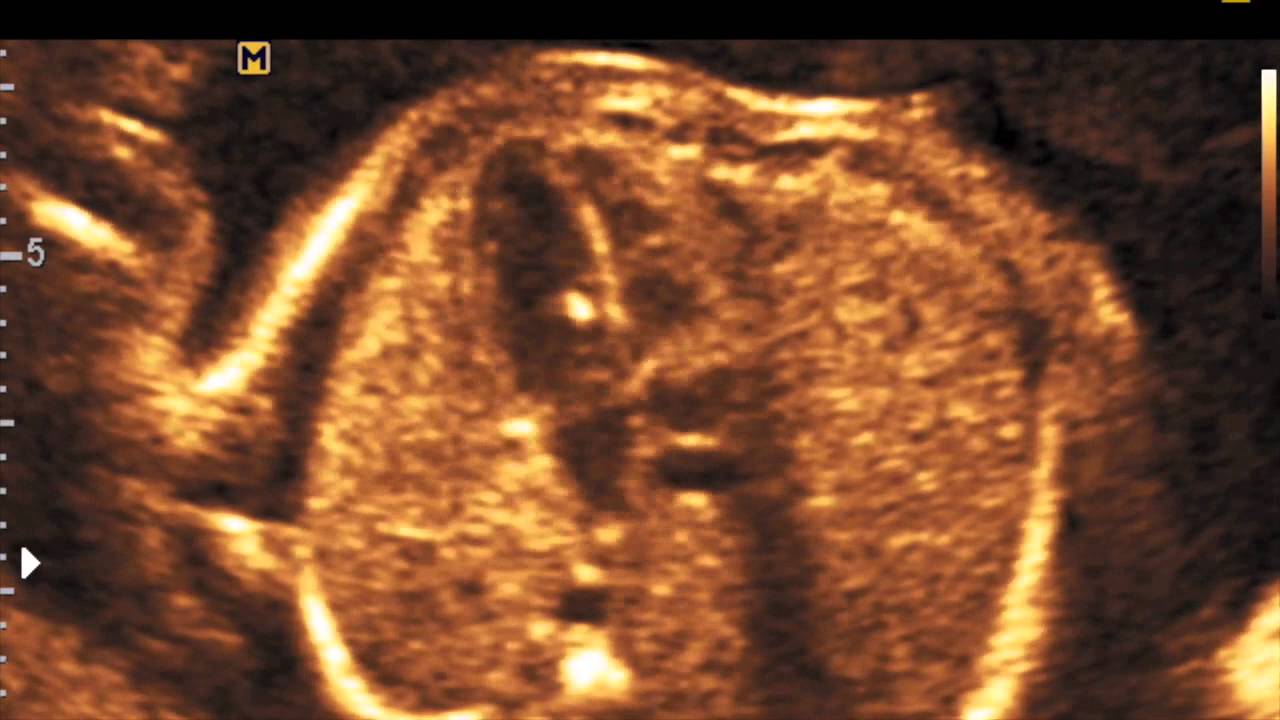

Focus Iperecogeno Ventricolo Sinistro

Golf Ball O Focus Iperecogeno Del Cuore Del Feto Cos E Tutto Mamma

Golf Ball Ventricolo Sinistro

Med00eco Golf Ball Youtube